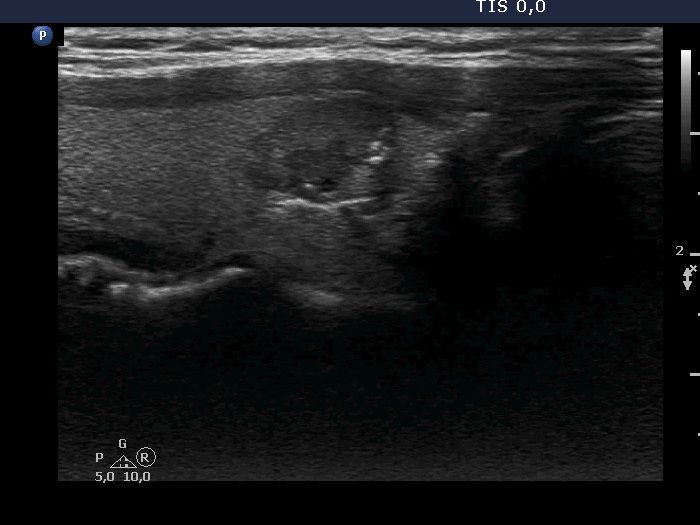

Ultrasonography. The thyroid was echonormal. There was a hypoechoic nodule in the right lobe. The lesion had lobulated margins and presented microcalcifications. The vascularity was non-specific.

We gave a common ultrasound-cytological diagnosis of suspicion of papillary cancer.